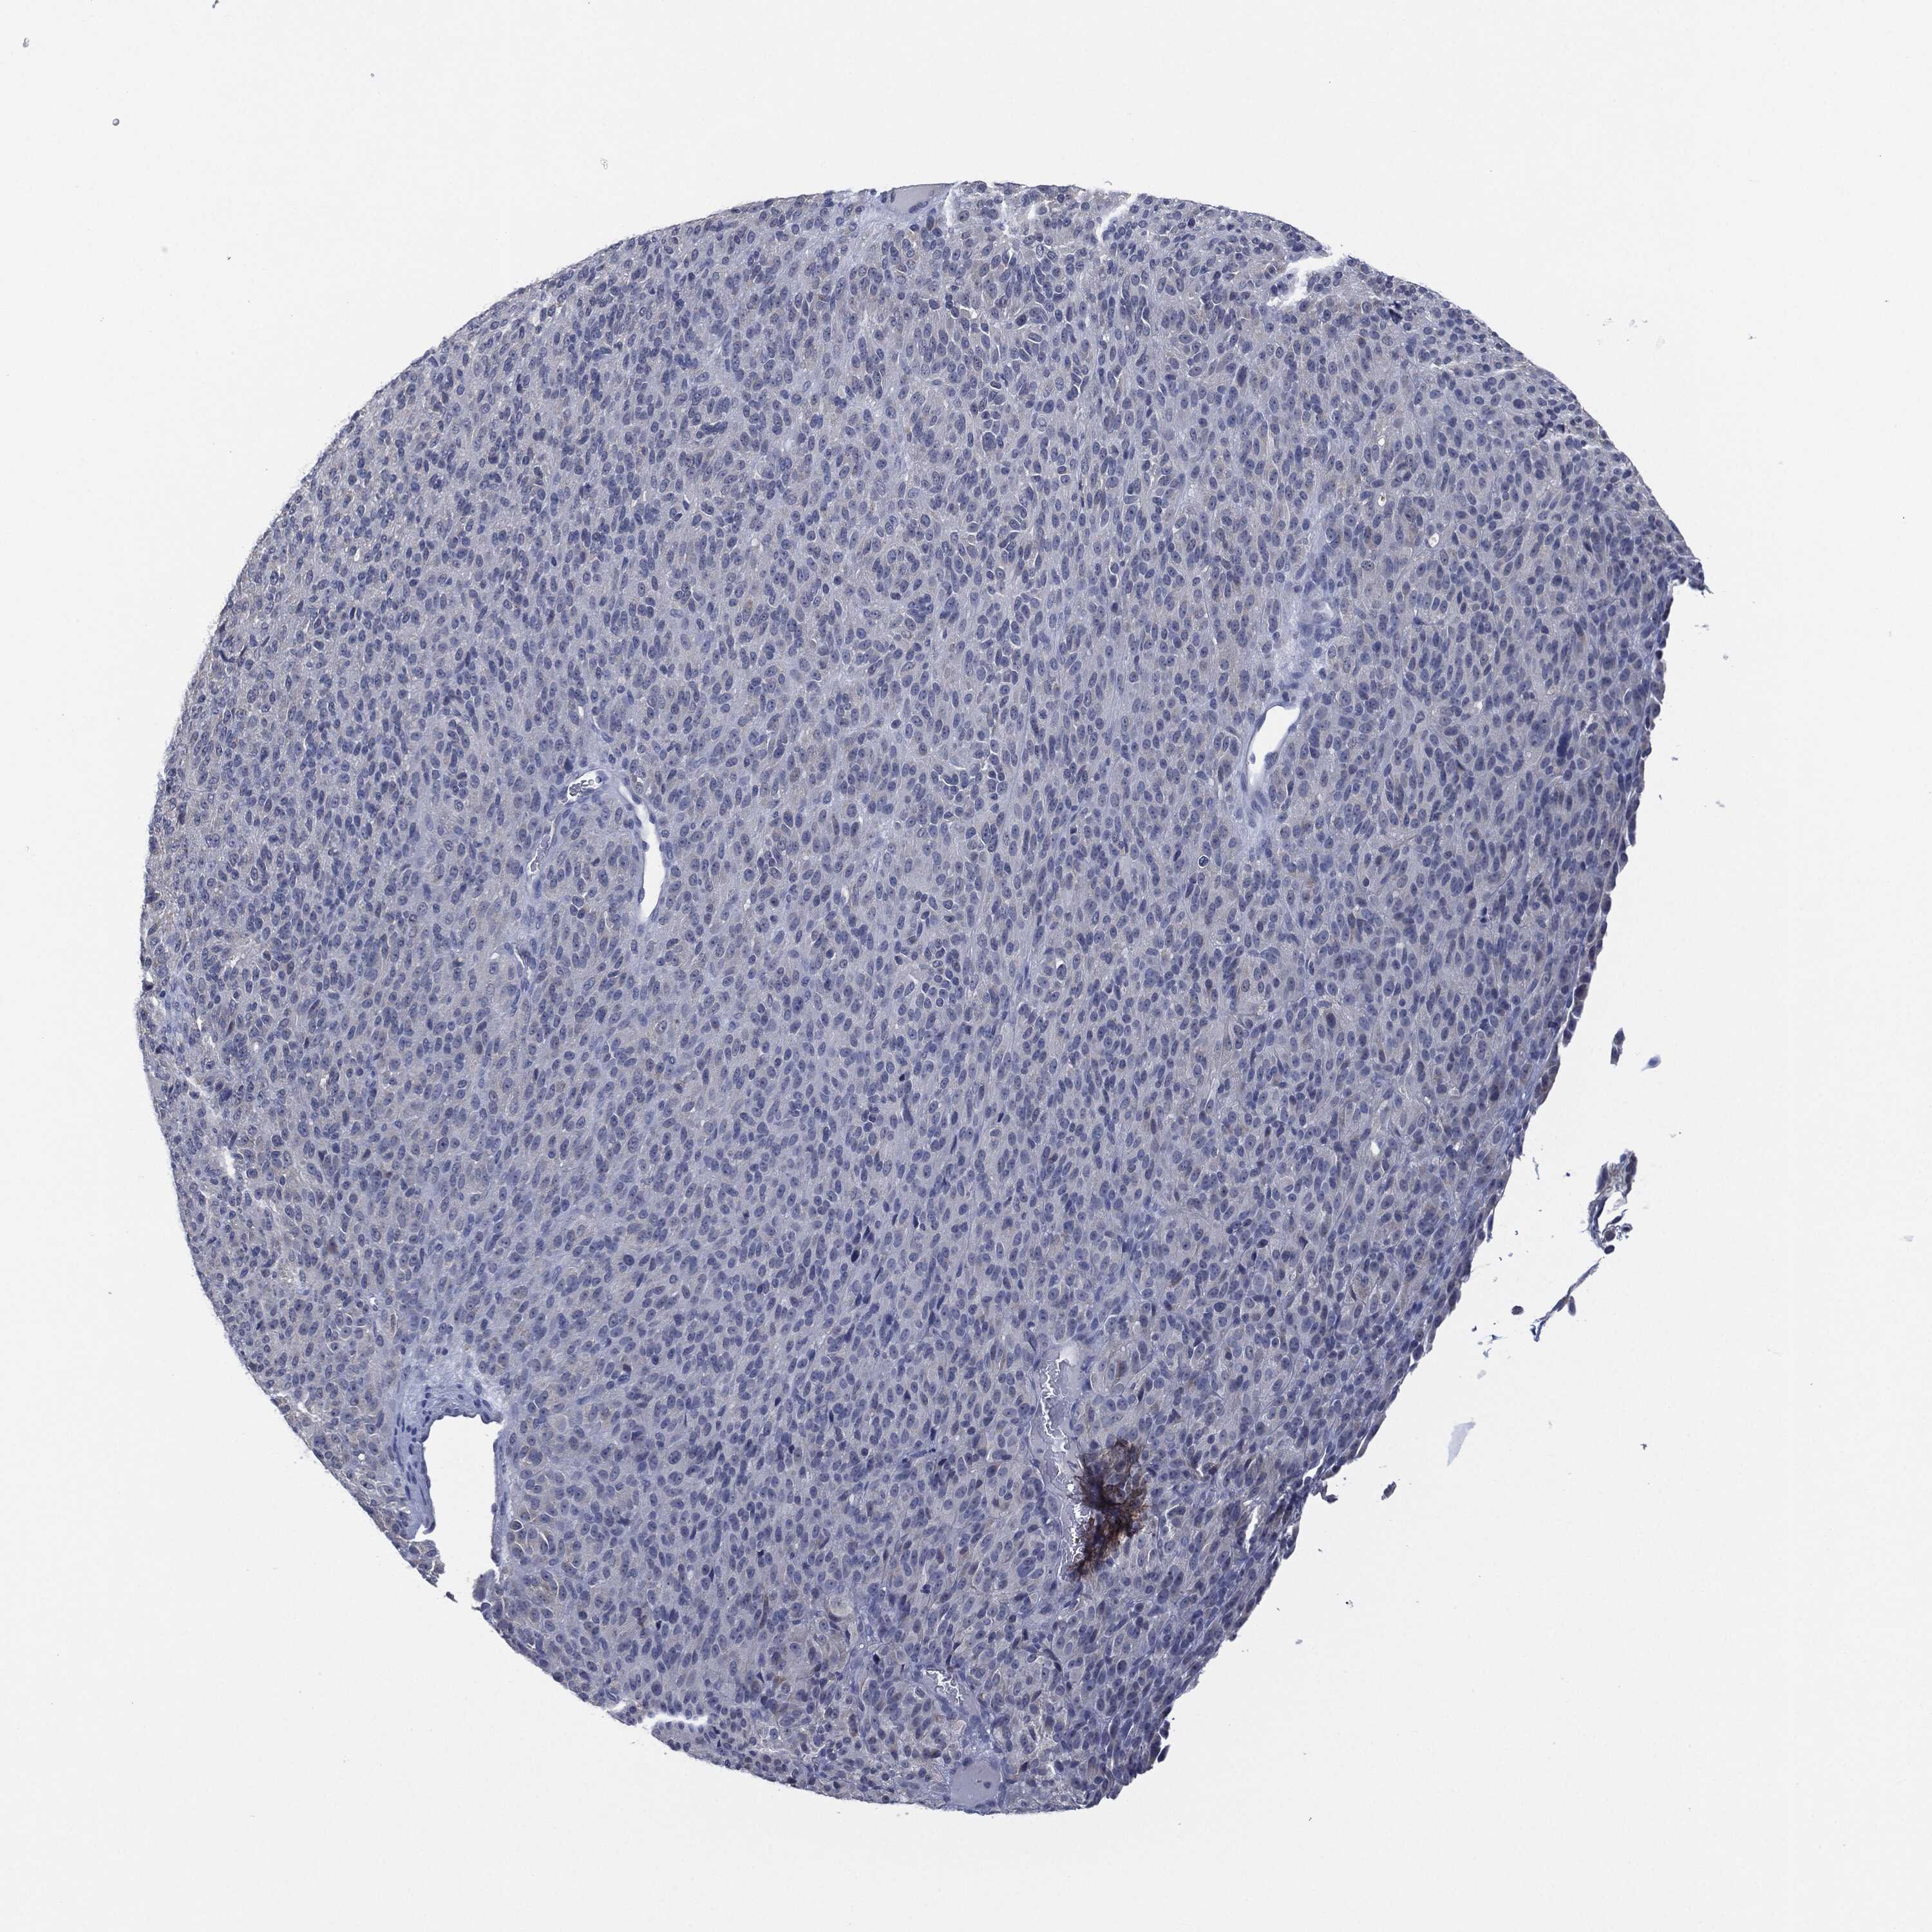

MELANOMA - Protein expressioni

A mouse-over function shows sample information and annotation data. Click on an image to view it in a full screen mode. Samples can be filtered based on level of antibody staining by selecting one or several of the following categories: high, medium, low and not detected. The assay and annotation is described here.

Note that samples used for immunohistochemistry by the Human Protein Atlas do not correspond to samples in the TCGA dataset.

Antibody stainingi

Antibody staining in the annotated cell types in the current human tissue is reported as not detected, low, medium, or high, based on conventional immunohistochemistry profiling in selected tissues. This score is based on the combination of the staining intensity and fraction of stained cells.

Each image is clickable and will lead to virtual microscopy that enables deeper exploration of all samples and also displays staining intensity scores, fraction scores and subcellular localization as well as patient and tissue information for each sample.

Antibody HPA001482

Antibody CAB009633

Antibody CAB080340

Staining

High

Medium

Low

Not detected

Intensity

Strong

Moderate

Weak

Negative

Quantity

>75%

75%-25%

<25%

None

Location

Nuclear

Cytoplasmic/membranous

Cytoplasmic/membranous,nuclear

Malignant melanoma, NOS

Malignant melanoma, Metastatic site